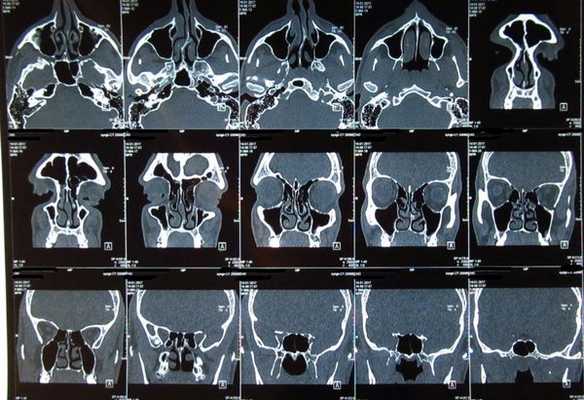

- Томографические исследования. Для оценки характера разрастания полипов применяют КТ или МРТ околоносовых пазух. С их помощью также можно выявить анатомические дефекты (искривление перегородки, кисты в синусах, сужение и деформацию носовых ходов).

- Аппаратные методы визуализации. В качестве базового исследования применяется рентгенография околоносовых пазух и орбиты. На снимках стенки этих образований могут быть утолщены, а полости затемнены, что является признаками воспалительного процесса и скопления гнойных масс. Также на рентгенограммах видны дефекты стенок, патологические соустья между глазницей и синусами. При недостаточной информативности метода назначаются МРТ, КТ лицевого скелета.

Диагностика синусита